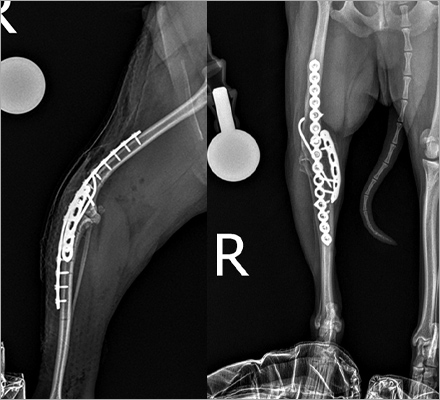

십자인대 질환

- TPLO

- 9살, 11kg, 아메리칸코커스패니엘

십자인대 질환에 대해 TPLO 수술을 진행하였습니다. 수술 직후 방사선에서 절골선이 보이지 않습니다.

정교하고 안정적인 수술로 다음날부터 산책이 가능합니다.

십자인대 질환

- 5 hole TPLO

- 11살 3kg 말티즈

다양한 회사의 플레이트 제품을 가지고 있어서 환자 맞춤으로 수술이 가능합니다.

일반적으로 TPLO 수술 시 6홀 플레이트를 사용하는데

이 환자의 경우 뼈가 작아 5홀 플레이트를 사용하여 교정하였습니다.

골절수술

- 요척골 단순골절

- 4살, 이탈리안그레이하운드

고난이도 상완골 원위부 골절

- IOHC, 상완골과골절

- 4개월 시추 2.6kg

고난이도 소형견 골절 수술

테디 수술 전

테디 수술 3주 후